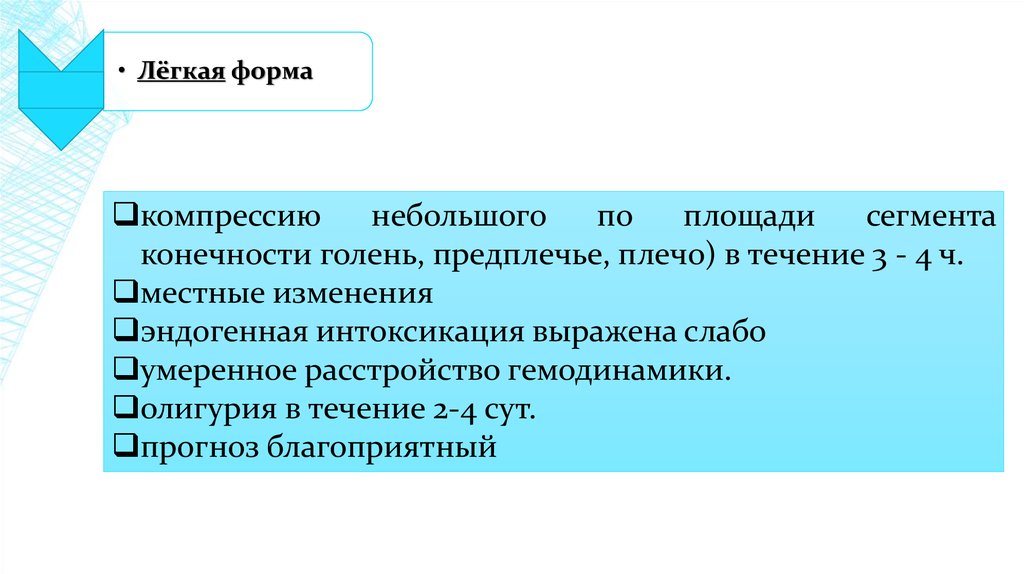

Классификация синдрома длительного раздавливания: основные категории и признаки